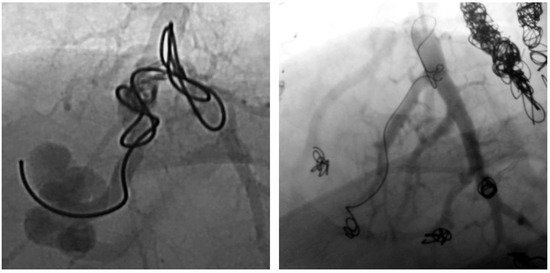

In another patient, however, the formation of collaterals between the intercostal and pulmonary arteries in the sense of aortopulmonary collaterals was detected (Figure 13 and Figure 14). Figure 15 also schematically shows the reperfusion mechanism of embolized PAVM with collateral formation.

Figure 13. MRA (left) with presentation of collateral vessels by the systemic circulation supplying the PAVM (open arrow) and confirmation by DSA (right).

Figure 14. DSA with presentation of embolized collaterals between intercostal and pulmonary arteries.